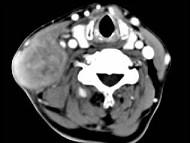

问题 65岁男性,吸烟史30余年,近半年来颈部出现疼痛性肿块,CT扫描如图所示,请选择最可能诊断()

选项 A.淋巴结核 B.血管瘤 C.神经鞘瘤 D.淋巴结转移瘤 E.软组织脓肿

答案 D